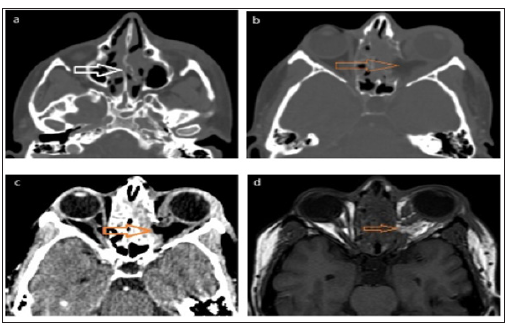

CT scan (Figure 2a) and MRI (Figure 2b) of the orbits, sinuses, and brain were performed. These showed, a large upper nasal septal defect and defective posterior 1/3 of left lamina papyracea. The left MR muscle and optic nerve were entrapped within the lamina papyracea defect with extra-orbital herniation of the intraorbital fat into the ethmoidal air cells. The sharp edge of the lamina papyracea defect was embedded within the optic nerve. The left MR and optic nerve were not seen continuous in any cut (injured versus masked by orbital fat). The origins of left SO and MR muscles were swollen (contusion). The muscle bellies of left extraocular muscles along the anterior 1/3 of the orbit were swollen. The right orbit was normal. The left maxillary sinus showed an antrostomy, with polypoidal thickening and retained secretions. The right maxillary antrum showed high density fluid that could be hemorrhagic. There was frontal and ethmoidal sinusitis, with rarefaction of the bony ethmoidal septa.

Figure 3: Post-operative imaging (a, b, c) non-contrast CT scan of the paranasal sinuses and orbit, axial cuts, (d) Non-contrast MRI T1WIs of the paranasal sinuses and orbit, axial cuts, showing defect in the bony nasal septum (white arrow), destruction of the inter-ethmoidal septae on the left side, defect in the medial orbital wall, loss of the continuity of the medial rectus muscle, loss of the continuity of the left optic nerve and its entrapment medially at the defect of the medial orbital wall (orange arrows), with blurring of the retro-orbital fat in MRI image.